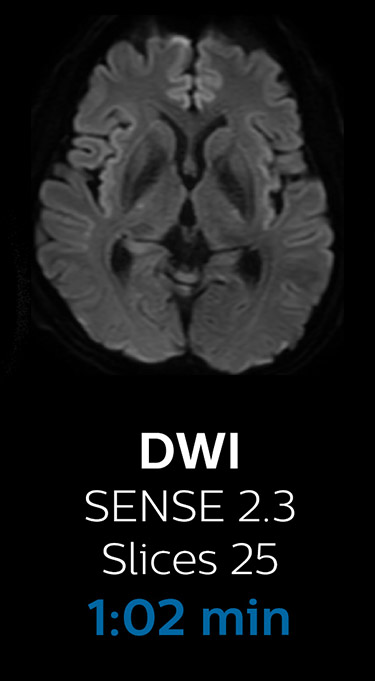

“We now only need about 10 minutes of scan time for a brain exam – and we still get the same amount of images and equal quality. We even managed to make a very useful improvement: we replaced the 43-second T2* FFE by a 43-second SWIp, which is more powerful for us in making confident diagnoses in certain patients.” “SWIp was not previously included in our standard protocol, because of its slightly longer scan time. SWIp provides high resolution 3D susceptibility weighted imaging in the brain, which helps to visualize small deoxygenated blood or calcium deposits. Now, with Compressed SENSE, we can perform 3D SWIp in only 43 seconds, so we have included SWIp instead of the 2D T2* FFE that we used previously. Without adding scan time, we now get SWIp images in every routine brain scan and it helps us increase our diagnostic confidence in certain cases.”

The most frequently used brain MRI examination at KNC included approximately 15 minutes of scanning time, and was quite comprehensive with fairly short scan times. When Compressed SENSE became available, its great impact on the brain exam quickly became clear.

Scanning time reduction in brain MRI with Compressed SENSE

With Compressed SENSE, the scan time for the routine brain examination at KNC was reduced from 15:48 to 10:19 minutes, which corresponds to 35% reduction.

Brain with Compressed SENSE

Ingenia 3.0T CX

Scan time 10:19 min.